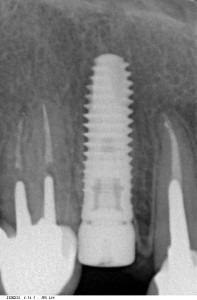

Вот пример:

![]() Сразу после имплантации — установлен имплантат одновременно с формирователем десны |